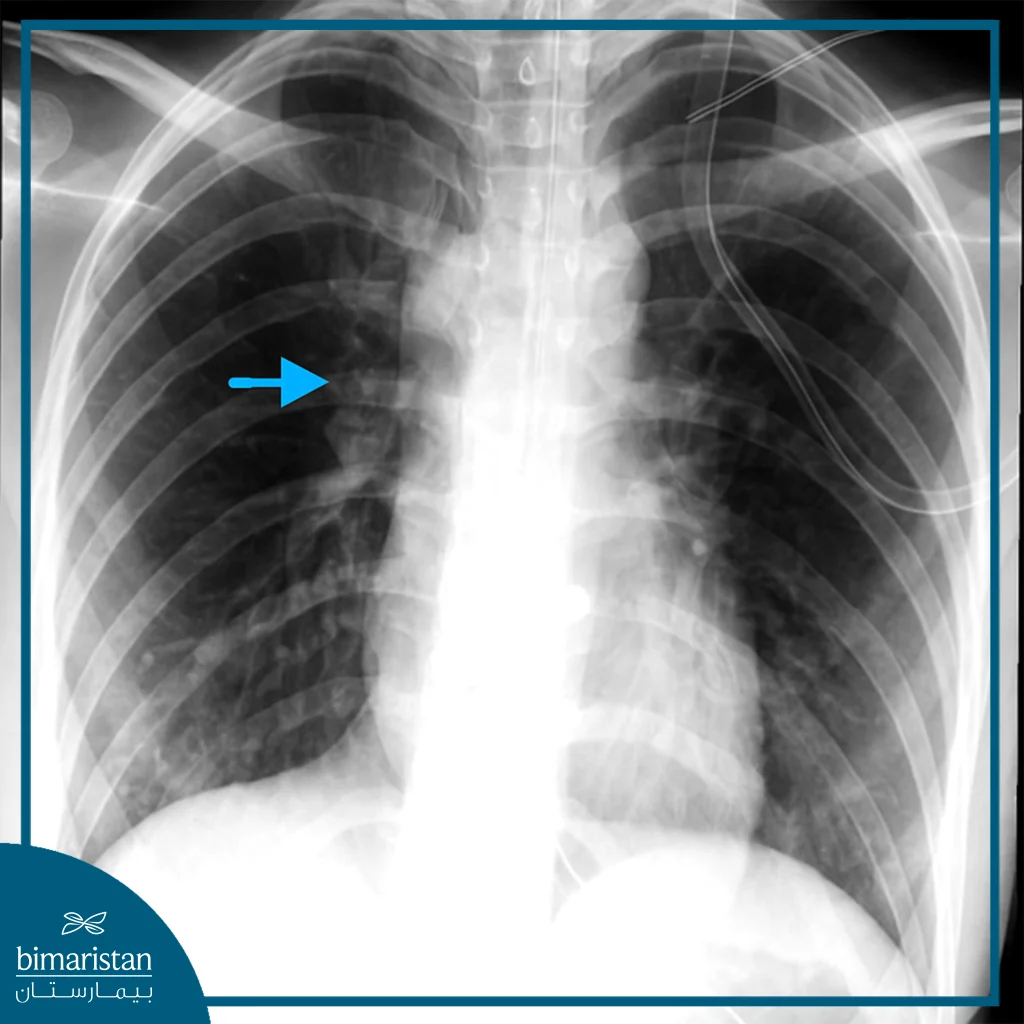

الأشعة السينية العادية (Chest X-ray)

تُعتبر الخطوة التصويرية الأولى وقد تُظهر وجود هواء في المنصف، انصباب جنبي، توسّع ظل المنصف، أو هواء تحت الجلد، أو هواء حر تحت الحجاب الحاجز في حالات الانثقاب البطني.